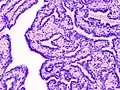

Histopathology of intraductal papilloma of the breast by excisional biopsy. Immunostaining for p63 protein.

Intraductal papillomas of the breast are benign lesions with an incidence of approximately 2-3% in humans.[1] They result from abnormal proliferation of the epithelial cells lining the breast ducts.[2]